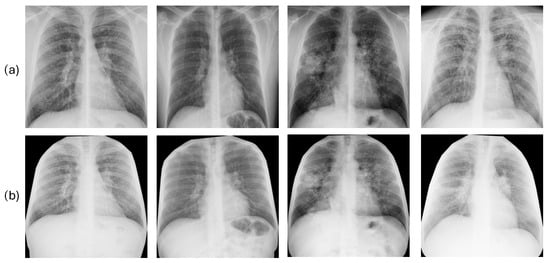

2.2. Image and Clinical Data

3.2. Ablation Study: Justification of Image Segmentation Method